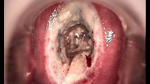

婦科leep錐切手術(shù) CIN2-3

• CIN 2-3CIN 2-3